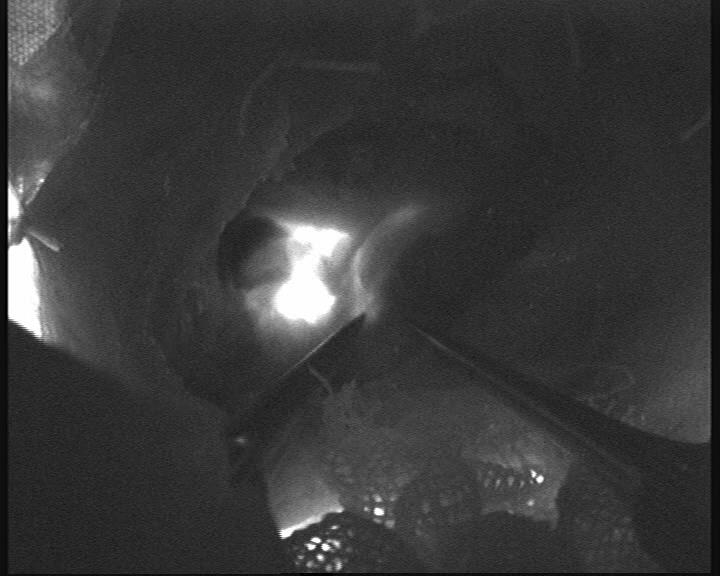

手术由神经外科缪星宇主任医师及马勃博士完成。团队在吲哚菁绿荧光显微镜引导下,通过颈部微小切口精准定位颈深淋巴结群与颈静脉,利用超显微外科技术,通过“八爪鱼”吻合方式吻合颈深淋巴-颈外静脉,建立两者间生理性引流通道,术中荧光造影引流通畅。双侧手术历时3小时余顺利完成,术中出血量不足10ml。术后患者生命体征平稳,术后2小时即恢复自主活动能力,焦虑情绪显著缓解。目前团队正密切监测其长期认知功能及影像学变化,进一步验证手术疗效。

图二 荧光显微镜显示颈深淋巴-颈外静脉吻合良好